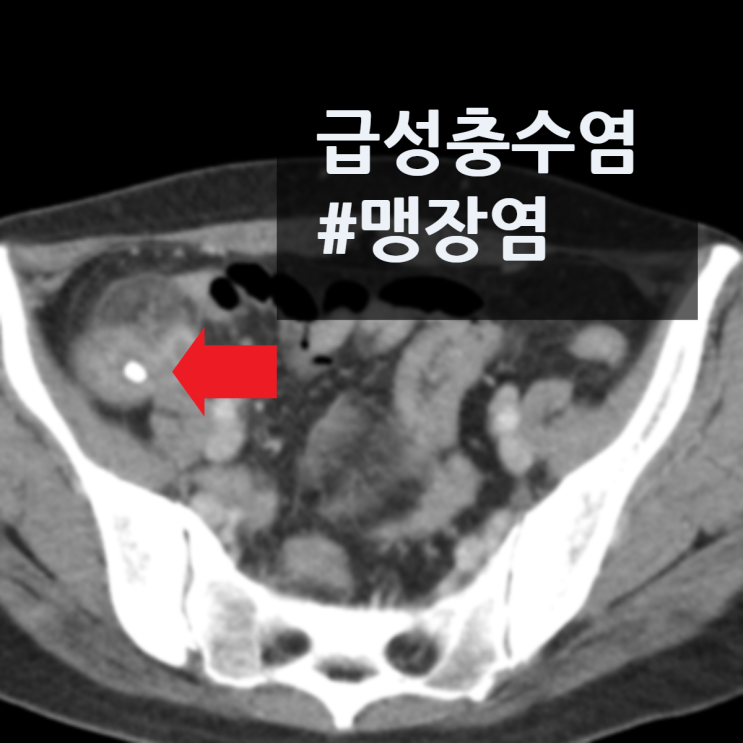

복부CT 사진을 보면 충수결석을 동반한 충수돌기 벽의 전반적 비후를 확인할 수 있습니다. 급성 충수돌기염(맹장염) 진단하여 추가 수술적 치료 위하여 상급병원 전원하였습니다.

• 복부CT: 급성충수염 #맹장염 소견 복부CT: 급성충수염 #맹장염 소견